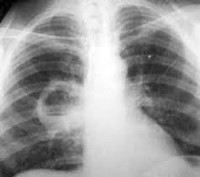

J85.3 Абсцесс средостения

Описание

Нет подробного описания, смотрите связи